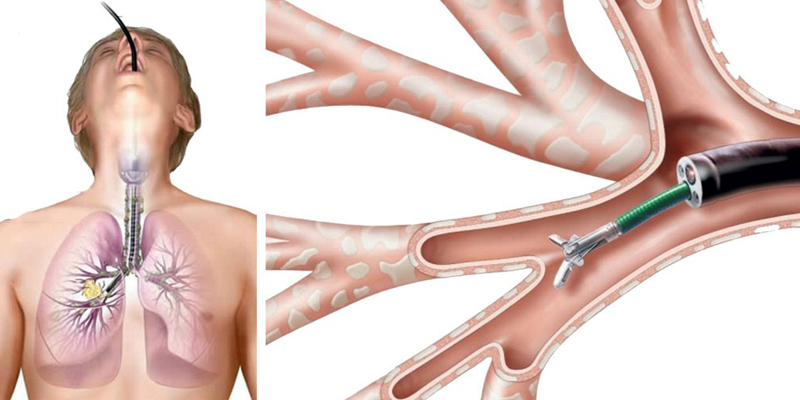

Specialist in Tuberculosis, Asthma, COPD, ILD, Pneumonia, Allergy, Bronchoscopy, Chest Diseases, Critical Care, and Sleep Disorders.